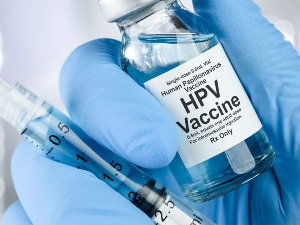

Код младих жена које су примиле ХПВ вакцину смртност од рака грлића материце пала на нулу

Ниједна жена старости од 20 до 24 године која је примила вакцину против хуманог папилома вируса (ХПВ)...

Код младих жена које су примиле ХПВ вакцину смртност од рака грлића материце пала на нулу

Ниједна жена старости од 20 до 24 године...